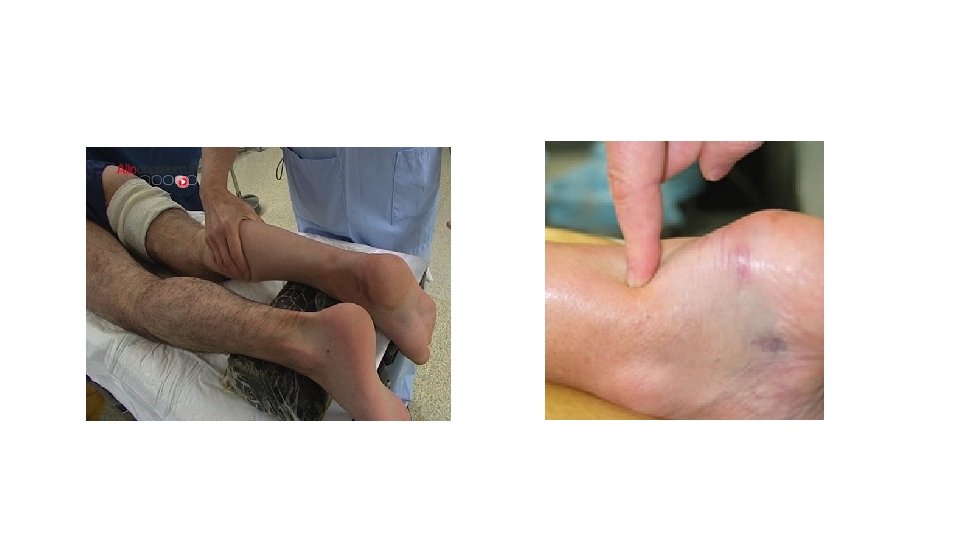

Clinique • 3 signes • Douleur Elle évolue en trois phases caractéristiques : douleur

Clinique • 3 signes • Douleur Elle évolue en trois phases caractéristiques : douleur au moment du traumatisme, puis elle se calme pendant un temps variable, puis reprend pour ne plus s'arrêter. • Gonflement Il est du à un œdème (réaction inflammatoire) et à l'hématome • Impotence fonctionnelle Sans radiographie, il est impossible d'éliminer une fracture associée.

Gestes • Ablation bagues et bijoux – A JEUN • Examen NEURO-VASCULAIRE • RICE

Gestes • Ablation bagues et bijoux – A JEUN • Examen NEURO-VASCULAIRE • RICE • Examen complémentaire